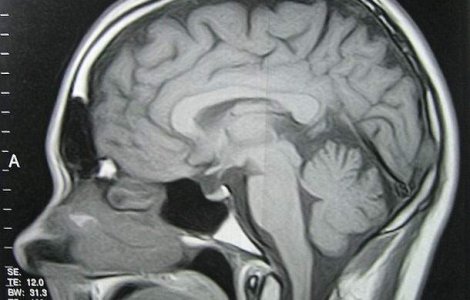

Mai multe vedete care joaca roluri de supereroi in filmele Marvel au ales sa aduca bucurie in viata unui tanar bolnav de cancer. Actorii s-au mobilizat si au transmis mesaje inspirationale unui baiat care are o tumoare pe creier.

Fostul dinamovist Cosmin Pascovici, a aflat, in 2006, ca fiul sau are o tumoare la creier. Desi copilul s-a vindecat, tratamentul costa 4000 de lei, lunar.

Senatorul Ted Kennedy, operat in iunie pentru ca avea o tumoare la creier, a revenit luni in Senatul american pentru prima data din luna iulie, relateaza NewsIn.